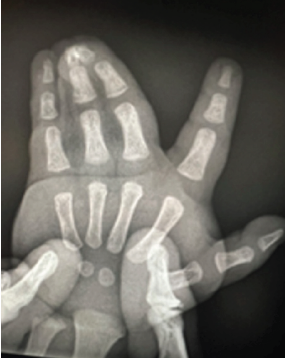

Reconstructive Surgery for Foot Ectrodactyly in an Adolescent Patient: A Case Report

Centenarro Jose S Meceda , Adrian Joseph C Tablante , Emiliano B Tablante ………………………………p.205-210